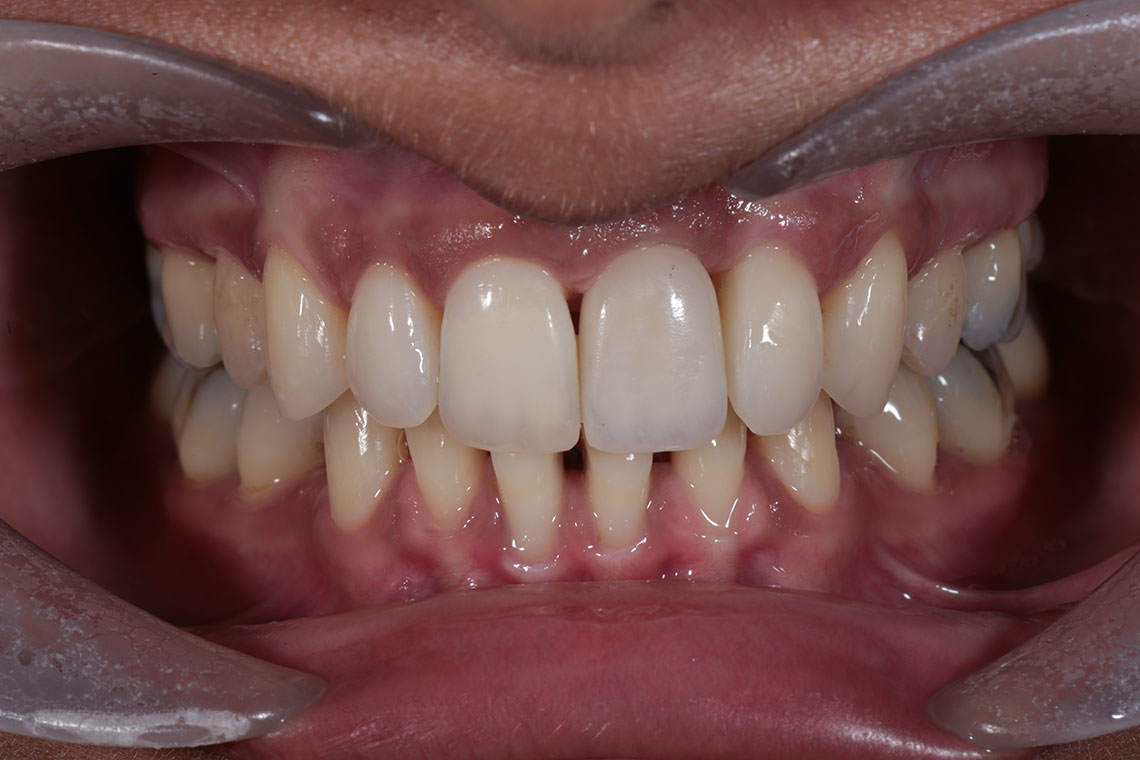

This lovely lady attended with very low confidence due to her teeth and smile. Gum disease and trauma had led to the teeth drifting. One of her front teeth was so loose that it needed to be replaced. We started by providing intensive treatment with our dental hygienist to treat the gum disease. Following this Invisalign® braces were used to align the teeth and the teeth were whitened. A dental implant was then placed to replace the loose front tooth and composite bonding was performed to the adjacent front tooth. The change in the patient’s confidence as a result of this work was breathtaking.

I have been extremely pleased with the treatments I have had here - Invisalign, composite bonding and whitening. My teeth look a million times better and the staff have been nothing but warm, friendly and professional.